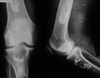

What distinctive vertebral body appearance is noted?

H-shaped vertebrae (DDx: Sickle cell anemia, thalassemia)

39

Give 2 differentials in order of likelihood.

1. Sickle cell anemia 2. Thalassemia

45

Name 4 major radiographic features on this radiograph.

- generalized osteopenia - widening of intercondylar notch - uniform jt space loss - ballooning of epiphysis

46

Give 2 differentials in order of likelihood. What 2 features support your diagnosis?

1. Hemophilia 2. JIA - ballooning of epiphysis - squaring of patella